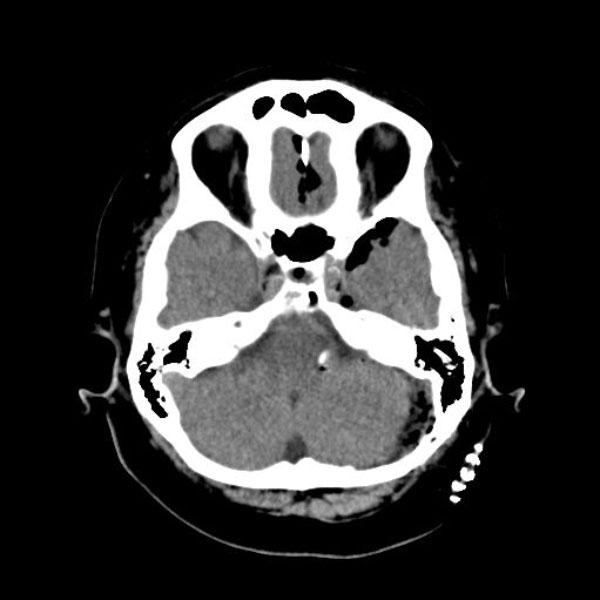

手術前

(MR1)

(CT)